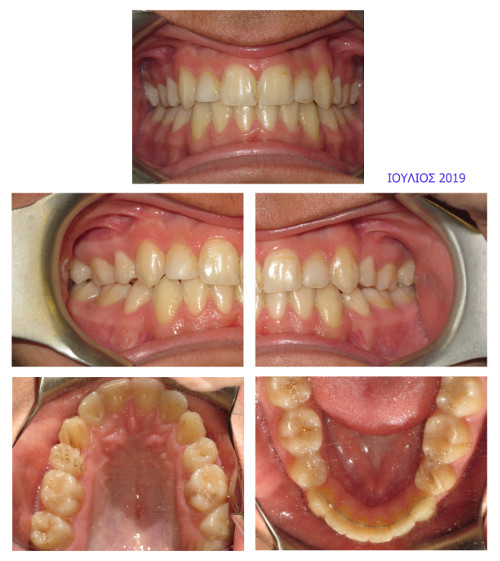

Τελικό Στάδιο

Επανέλεγχος 3 χρόνια μετά